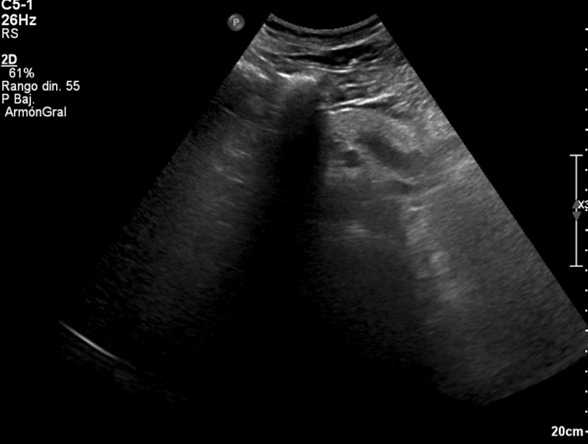

El paciente presentó mejoría rápida del dolor torácico tras analgesia, permaneciendo hemodinámicamente estable y sin nueva sintomatología. Los exámenes de laboratorio y la radiografía de tórax no mostraron alteraciones. La ecografía torácica/abdominal evidenció un situs inversus total como hallazgo incidental, sin relación con el cuadro clínico. Durante la observación evoluciona asintomático, con adecuada ventilación y sin dolor, por lo que se decide alta con educación respecto a su condición anatómica y recomendaciones para seguimiento.

La integración de un examen físico completo, en conjunto con los hallazgos característicos del electrocardiograma y la confirmación estructural mediante ecocardiograma, permite establecer con precisión el diagnóstico de situs inversus. El examen físico orienta desde los primeros momentos al identificar la posición anómala de los ruidos cardíacos y, el electrocardiograma aporta patrones eléctricos sugestivos de inversión anatómica. Finalmente, el ecocardiograma y Rx confirman la disposición especular de las estructuras torácicas y cardíacas.